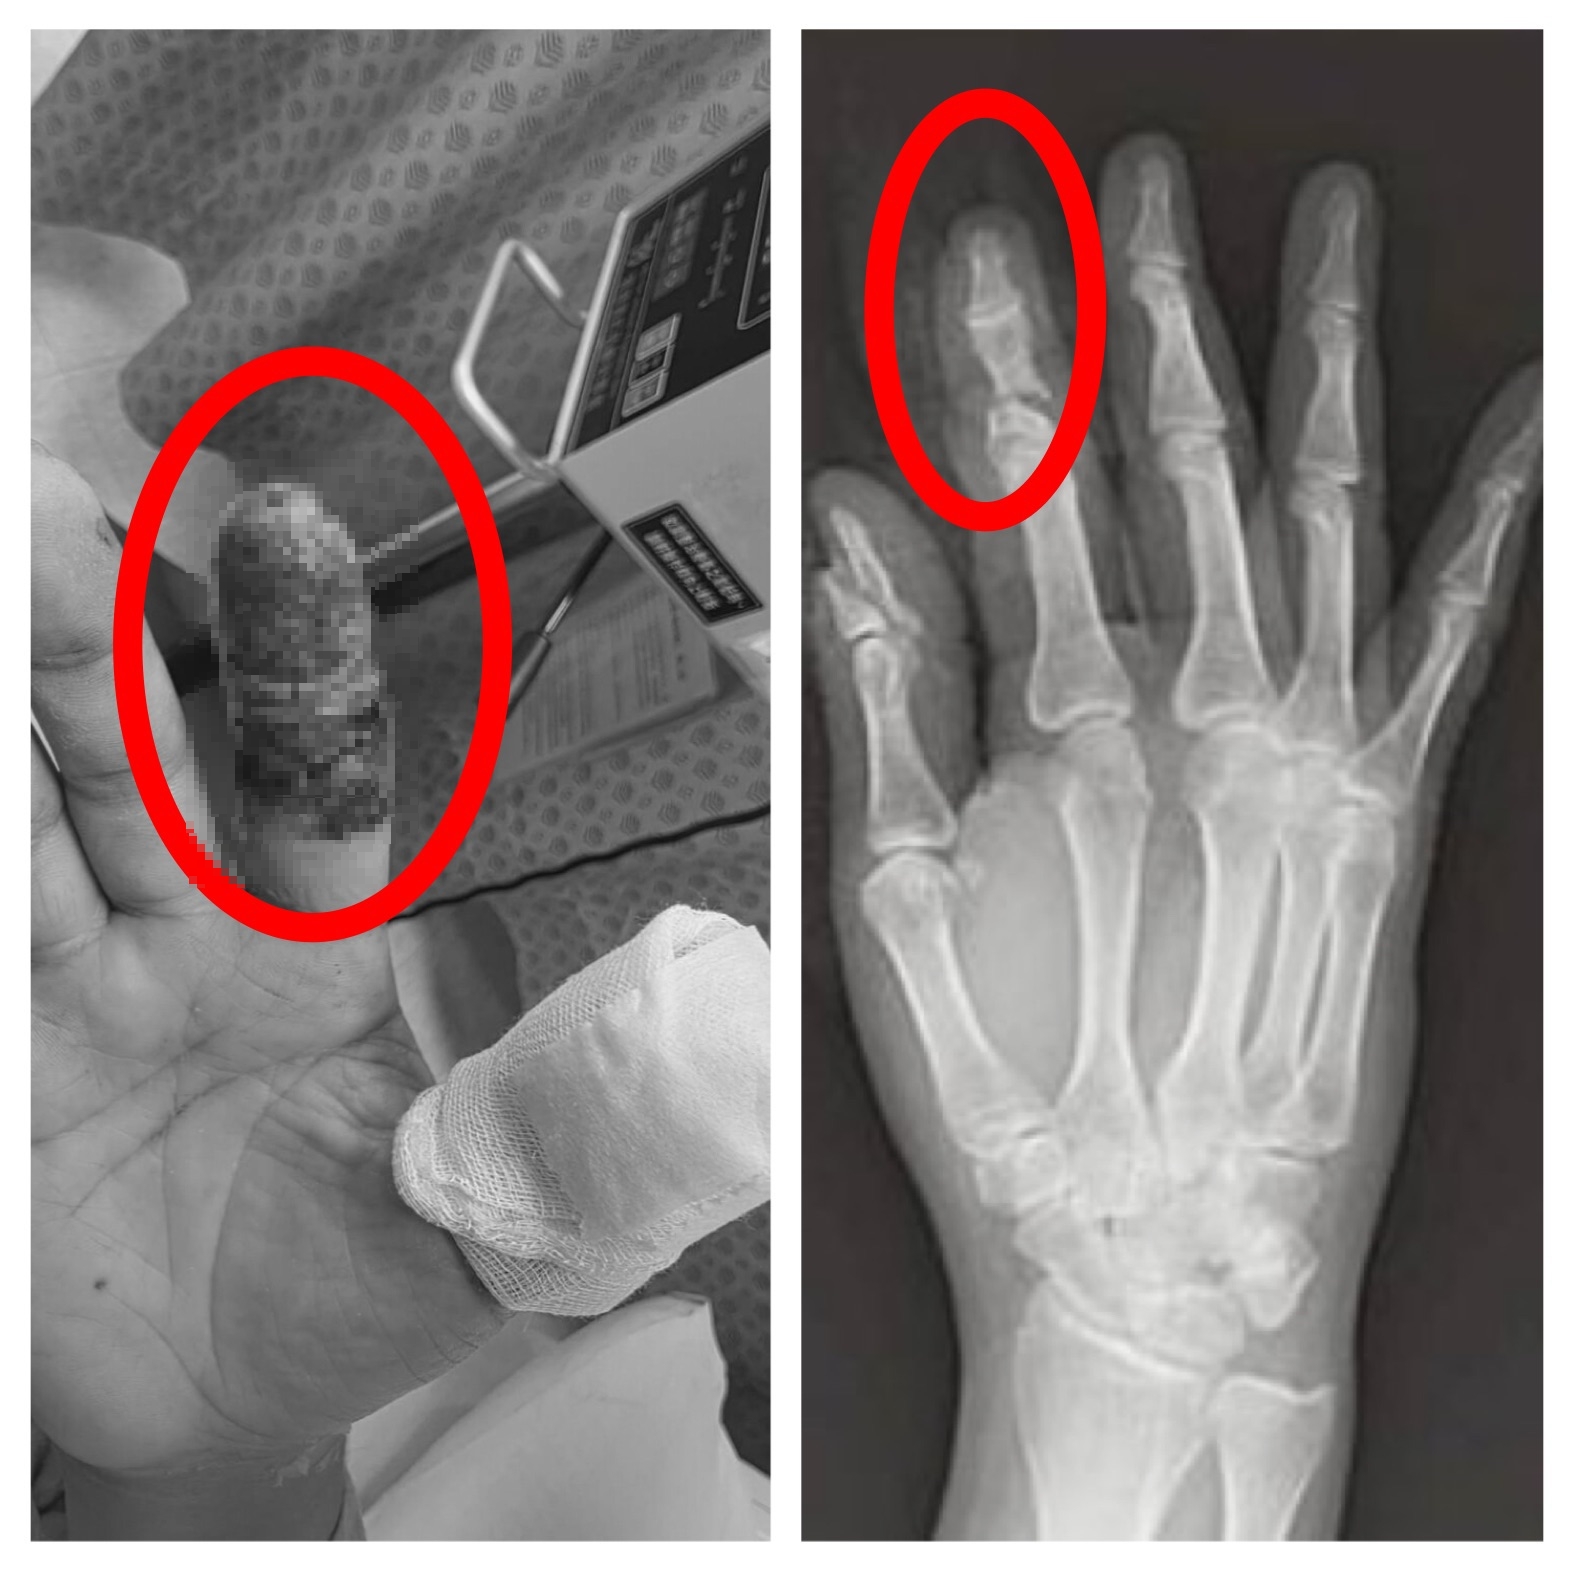

【Lai傳媒、記者爆料網/周庭慶/台中報導】豐原一名45歲林姓男子日前操作大型無人機時發生意外,高速旋轉的螺旋槳瞬間擊中右手,食指幾乎完全斷離,僅剩少量皮膚相連,傷勢嚴重,緊急送往衛生福利部豐原醫院救治,經外科醫師陳明澤評估屬重大手指創傷,若血流未恢復恐須截指,立即進行清創與重建手術,透過顯微技術接合受損血管與組織,成功建立循環,為後續組織存活爭取關鍵時間。患者住院期間長達一個月,最終順利出院,成功保住手指外觀與功能。

林姓男子日前操作大型無人機時發生意外,高速旋轉的螺旋槳瞬間擊中右手,食指幾乎完全斷離。翻攝畫面

豐原一名45歲林姓男子日前操作大型無人機時發生意外,高速旋轉的螺旋槳瞬間擊中右手,險些斷指。翻攝畫面